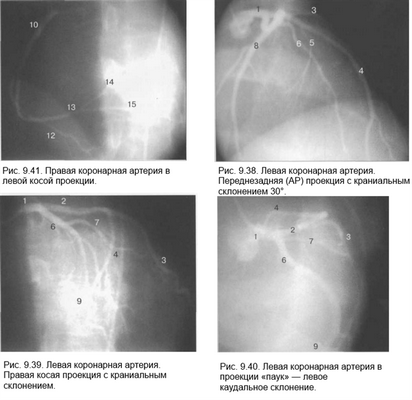

Здесь и на рис. 9.38—9.46:

1 — левая коронарная артерия; 2 — проксимальная треть передней нисходящей артерии; 3 — первая диагональная ветвь передней нисходящей артерии; 4 — дистальная часть передней нисходящей артерии; 5 — септальная ветвь передней нисходящей артерии; 6 — проксимальная часть огибающей артерии; 7 — первая маргинальная ветвь огибающей артерии; 8 — промежуточная артерия; 9 — дистальная часть огибающей артерии; 10 — проксимальная часть правой коронарной артерии; 11 — ветвь синусного узла правой коронарной артерии; 12 — ветвь острого края правой коронарной артерии; 13 — бифуркация правой коронарной артерии; 14 — правая левожелудочковая ветвь правой коронарной артерии; 15 — задняя нисходящая ветвь правой коронарной артерии.

Фиксация изображения коронарных артерий производится последовательно в нескольких плоскостях.

На рис. 9.37—9.41 изображены левая и правая коронарные артерии и их ветви при равномерном типе коронарного кровообращения в обычной последовательности проекций.

На следующих рисунках представлены два типа коронарного кровообращения — правый и левый и характеризующиеся неравномерным развитием правой коронарной и огибающей (ветвь левой коронарной артерии) артерий. При левом типе отмечается выраженная периферия огибающей артерии при значительной гипоплазии правой коронарной артерии. При правом типе чаще всего хорошо развита маргинальная ветвь и гипоплазирована основная ветвь огибающей артерии. Периферия правой коронарной и, в особенности, правая левожелудочковая ветвь значительно выражены и превосходят огибающую по размерам зоны кровоснабжения.

Рис. 9.42-9.44 — левый тип коронарного кровообращения.

Рис. 9.45 и 9.46 — правый тип коронарного кровообращения.

Рис. 9.42. Левая коронарная артерия. Правая косая проекция.

Рис. 9.43. Левая коронарная артерия. Проекция «паук».

Рис. 9.44. Правая коронарная артерия. Левая косая проекция.

Рис. 9.45. Левая коронарная артерия в правой косой проекции.

Рис. 9.46. Правая коронарная артерия в переднезадней проекции.